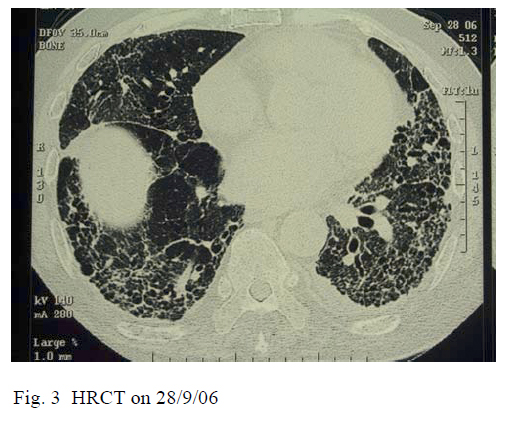

The patient improved both clinically and radiologically and was transferred to convalescence hospital for rehabilitation on day 10 of admission. Oxygen was eventually weaned off. He was followed up in our outpatient respiratory clinic and prednisolone was tailed down to 10 mg daily together with addition of azathioprine 25 mg daily. Physical examination on follow-up showed the normal power of the upper limbs with no proximal muscle weakness. HRCT thorax at 3 months showed that the ground glass opacities had already resolved with residual subpleural fibrosis and traction bronchiectasis (Fig. 3).